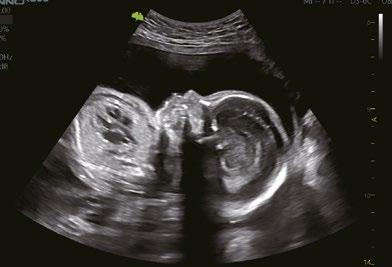

Eine neue 3D-Rendering-Technologie, die es dem Benutzer ermöglicht, die Position und Richtung der virtuellen Lichtquellen individuell anzupassen, wodurch die Details der inneren Strukturen deutlicher dargestellt und die dreidimensionale Wahrnehmung verbessert werden.

Color 3D-Rendering-Technologie für eine verbesserte 3D Visualisierung und Strukturdarstellung, z.B. bei der Nabelschnur.